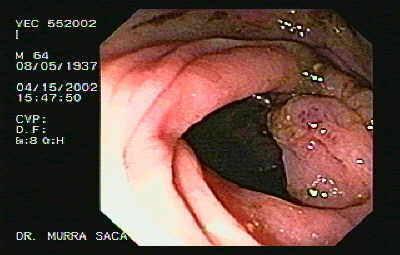

Upper GI endoscopy

This is done to detect the presence and extent of ulceration and tumor in GIT.